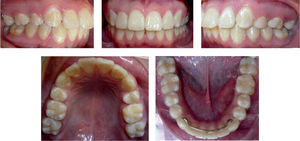

El examen intraoral revela que el paciente presenta clase II molar y clase II canina bilateral, apiñamiento moderado anterior superior e inferior, línea media maxilar desviada a la derecha, sobremordida horizontal de 5mm, sobremordida vertical de 3mm, la arcada de forma cuadrada en maxilar, así como la arcada de forma ovalada en mandíbula y los tejidos se observan sanos periodontalmente (Figura 2).

En el análisis de modelos se obtuvo un resultado de discrepancia dental en relación con el espacio disponible de -7mm en maxilar y -3mm en arco mandibular (Figura 4).